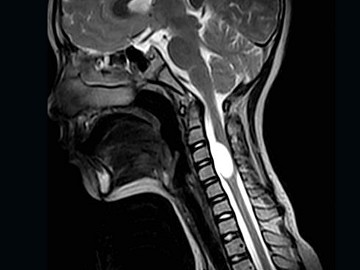

女,9岁,颈部疼痛、活动受限2个月,MRI检查如图,最可能的诊断为()

A.室管膜瘤

B.星形细胞瘤

C.神经鞘瘤

D.髓内囊肿

E.脊膜瘤